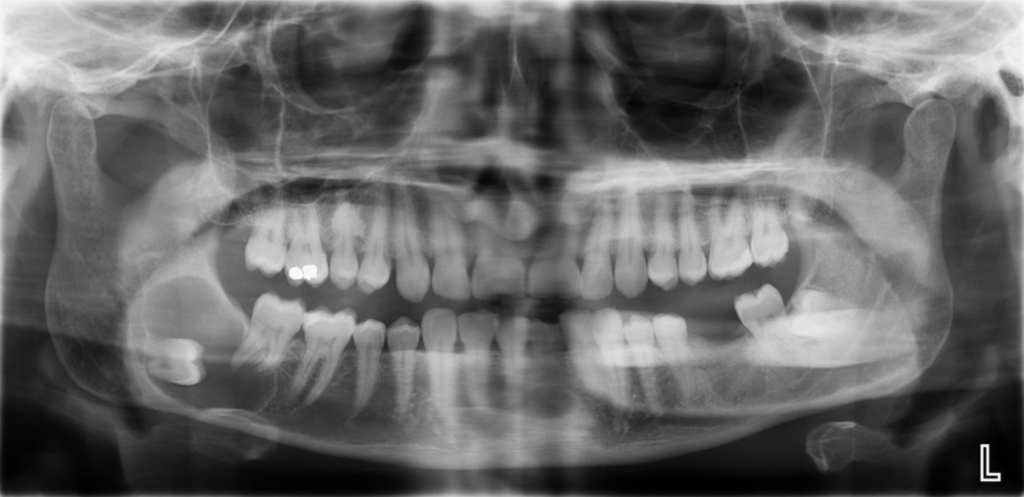

不時有病人在照X光檢查時才意外發現阻生智慧齒出現問題,所以單憑痛楚或牙肉發炎等症狀,並不能準確反映牙齒是否健康良好。

圖二:X光顯示阻生智慧齒令到前面牙齒嚴重蛀壞